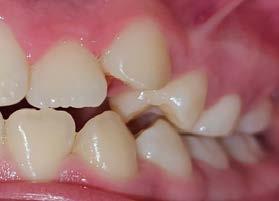

Se observó en la evaluación asimetría facial, tercio inferior aumentado, en la regla de quintos las líneas interpupilares no coinciden con la comisura labial, muestra 2/3 de las coronas superiores al sonreír y perfil retrusivo ocasionado por la distoclusión mandibular (Figura 1).

Su fonación no es clara, ya que presenta congestión nasal y hábito de lengua. Las fotografías intraorales de inicio se muestran en la Figura 2

Figura 2. Fotografias intraorales: A) fotografía de en oclusión, mordida abierta, línea media desviada. B) fotografía lateral, clase II subdivisión I.